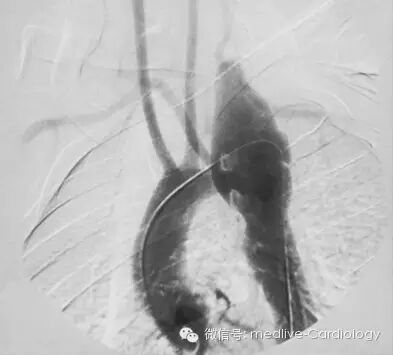

血管造影是诊断主动脉夹层的传统参考标准。它可以实时观察,并且由于截至主动脉弓的血管易于评估,因此可以为外科手术方案提供极佳的辅助信息。造影中可以直接观察到真假两腔。这一操作十分依赖术者的技术,因为夹层恶化是血管造影的常见并发症。有了CT和MRI检查,血管造影常仅限于无手术指征的患者使用。